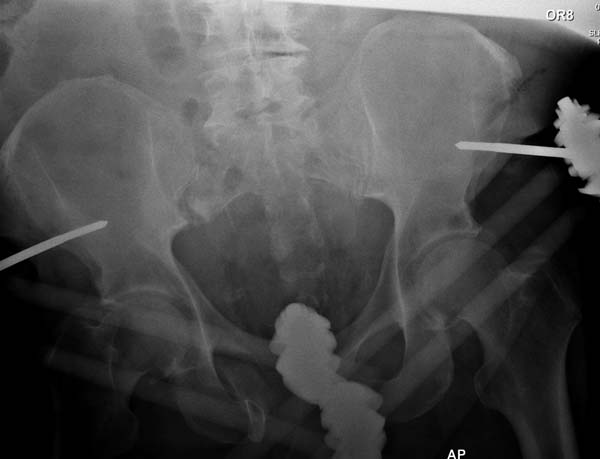

Здесь снимки, которые показывают направление стержня, а также идею

репозиции вытяжением. На рентгенопроницаемых столах имеется возможность

установить дополнительную раму, где по желанию можно увеличить или

уменьшить высоту угла вытяжения. Для репозиции таза больной в положение

на спине, стержень для вытяжения остается во время операции. Система

подойдет для тракции головки бедра из вертлужной впадины, и для этого

стерильная веревка и Synthes Universal Chuck with T-Handle.

окончательная фиксация. Первые снимки после стабилизации таза, и другие,

где показаны (параллельные) правильная установка на AIIS т.е на месте

прикрепления прямой мышцы бедра. Ампутация закончена костно пластическим